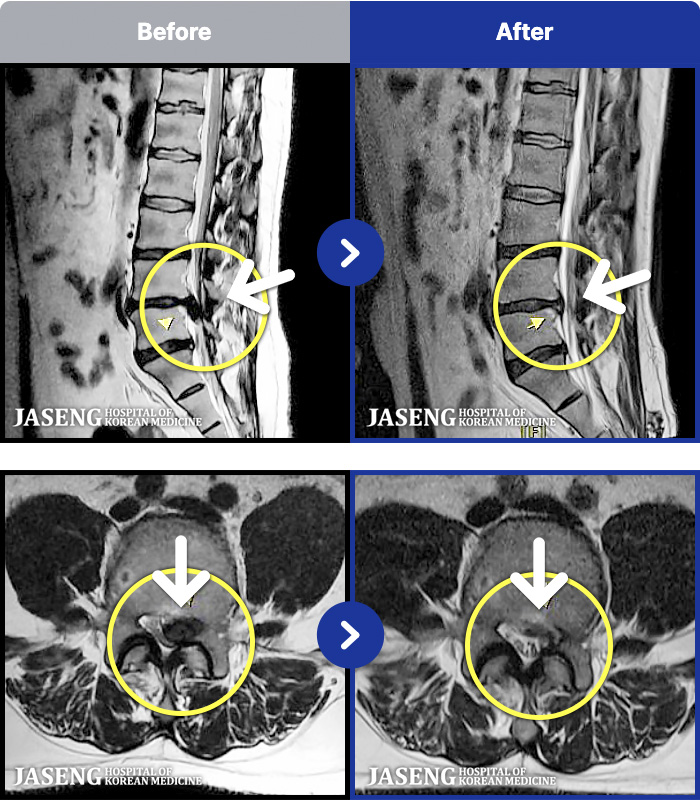

"또 아팠지만 다시 걷게 됐습니다" 허리디스크 재발을 극복한 이야기